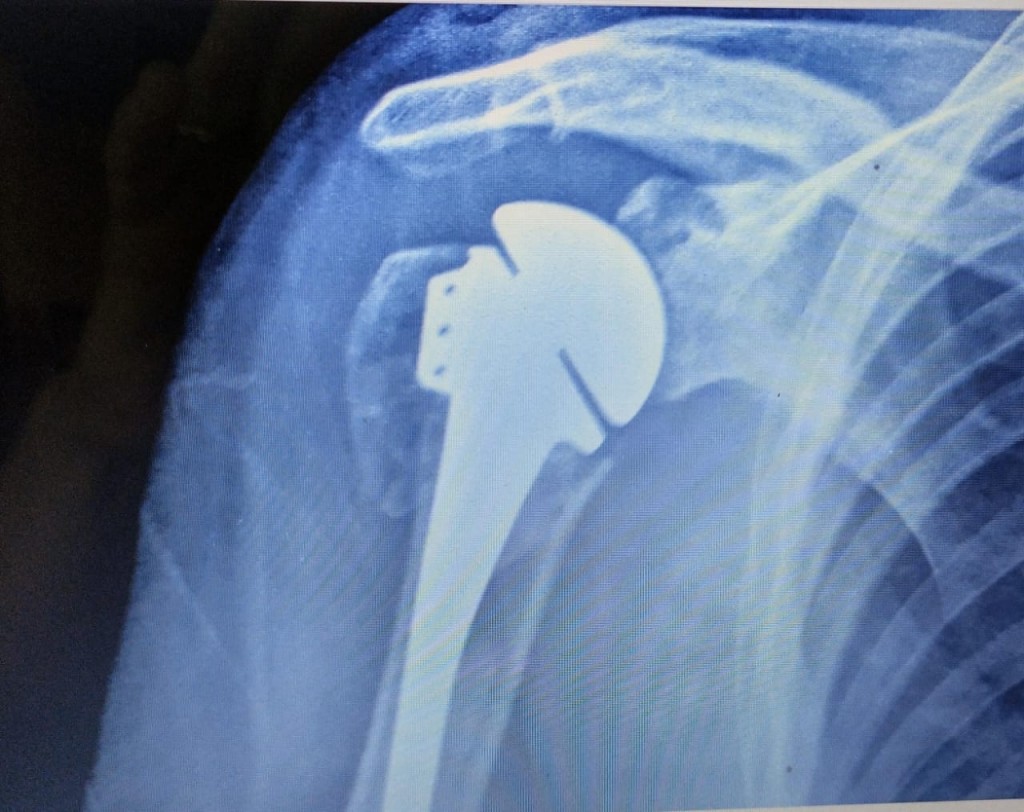

Y agregaron que en nuestro HAC se atienden desgarros, luxaciones, fracturas complejas, se realizan prótesis osteosíntesis, plastias de reparación de desgarros y lesiones capsulares por luxaciones, entre otros; los cuales se pueden llevarse a cabo gracias a que esta institución cuenta con la infraestructura, instalaciones y principalmente, con el recurso humano formado, médicos con nivel profesional que facilita en forma multidisciplinaria el enfoque y tratamiento del paciente que ingresa con una patología de articulación de hombro o de codo.